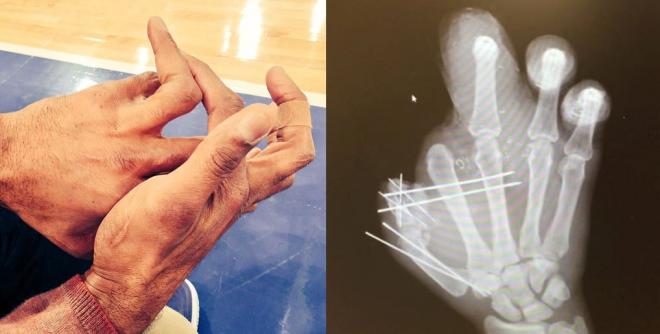

Igen, az ott egy gyűrűs ujj, ami egy sérülés következtében viszonylag könnyen hajtogathatóvá vált. A liga sackrekordere elmondása szerint annak idején kicsit pánikba esett, amikor a pályáról lefutva észlelte, hogy „az egyik elment vadászni”, de mivel az ilyen sérüléseket a kispadnál kiröhögik, gyorsan visszatette a helyére a kificamodott ujjat, majd ment vissza játszani. Strahan egyébként nem először mutatta meg „trükkjét”, íme egy videó azoknak, akiknek erősebbek az idegei vagy gyengébbek az ízületei.

Másik Óriásokhoz, illetve ujjakhoz kapcsolódó hírünk is egy defensive endet érint. Jason Pierre-Paul ugyanis beperelte Adam Scheftert és az ESPN-t, amiért illegális úton megszerzett orvosi dokumentumokat hoztak nyilvánosságra a játékos tűzijáték-balesetét követően. A Jackson Memorial Kórházból kiszivárogtatott leletek csak Schefter accountján keresztül 4 millió követőhöz jutottak el, a valóságban viszont alighanem még többen láthatták az orvosi papírokat. A játékos felháborodása és pereskedése szerintünk teljesen érthető, még akkor is, ha múlt héten saját maga cserélte le a Twitter profilképét egy baleset utáni röntgenképre, hiszen az orvosi titok akkor is orvosi titok, ha valaki híres sportoló, közszereplő.